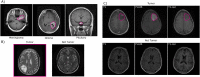

Early detection and diagnosis of brain tumors are crucial to taking adequate preventive measures, as with most cancers. On the other hand, artificial intelligence (AI) has grown exponentially, even in such complex environments as medicine. Here it's proposed a framework to explore state-of-the-art deep learning architectures for brain tumor classification and detection. An own development called Cross-Transformer is also included, which consists of three scalar products that combine self-care model keys, queries, and values. Initially, we focused on the classification of three types of tumors: glioma, meningioma, and pituitary. With the Figshare brain tumor dataset was trained the InceptionResNetV2, InceptionV3, DenseNet121, Xception, ResNet50V2, VGG19, and EfficientNetB7 networks. Over 97 % of classifications were accurate in this experiment, which provided a network's performance overview. Subsequently, we focused on tumor detection using the Brain MRI Images for Brain Tumor Detection and The Cancer Genome Atlas Low-Grade Glioma database. The development encompasses learning transfer, data augmentation, as well as image acquisition sequences; T1-weighted images (T1WI), T1-weighted post-gadolinium (T1-Gd), and Fluid-Attenuated Inversion Recovery (FLAIR). Based on the results, using learning transfer and data augmentation increased accuracy by up to 6 %, with a p-value below the significance level of 0.05. As well, the FLAIR sequence was the most efficient for detection. As an alternative, our proposed model proved to be the most effective in terms of training time, using approximately half the time of the second fastest network.